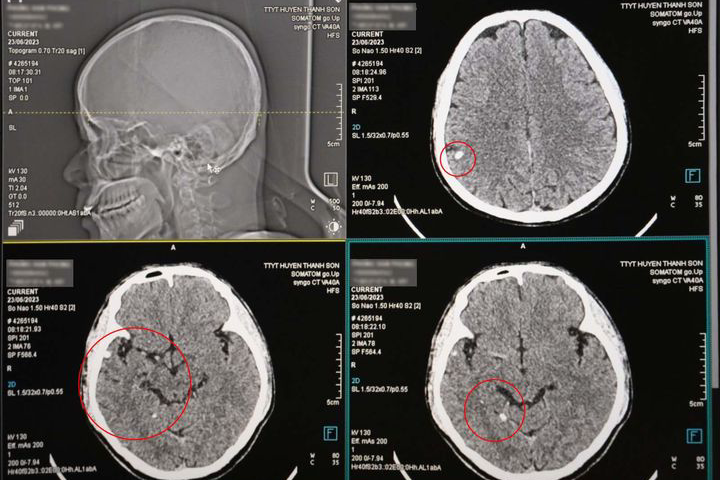

Sau khi chụp CT, các bác sĩ Khoa Chẩn đoán hình ảnh - Thăm dò chức năng phát hiện trong sọ não bệnh nhân có hình ảnh nang ký sinh trùng (ấu trùng sán não) tại nhiều vị trí khác nhau.

Bác sĩ chuyên khoa I Đinh Đại Lâm - Trưởng khoa Chẩn đoán hình ảnh - Thăm dò chức năng, Trung tâm Y tế huyện Thanh Sơn, cho biết, kén sán não là bệnh nhiễm trùng hệ thần kinh do ấu trùng sán dây lợn sống ký sinh ở người gây ra. Bệnh kén sán não nếu không được phát hiện và xử trí sớm sẽ dẫn tới nhiều biến chứng cực kỳ nguy hiểm.